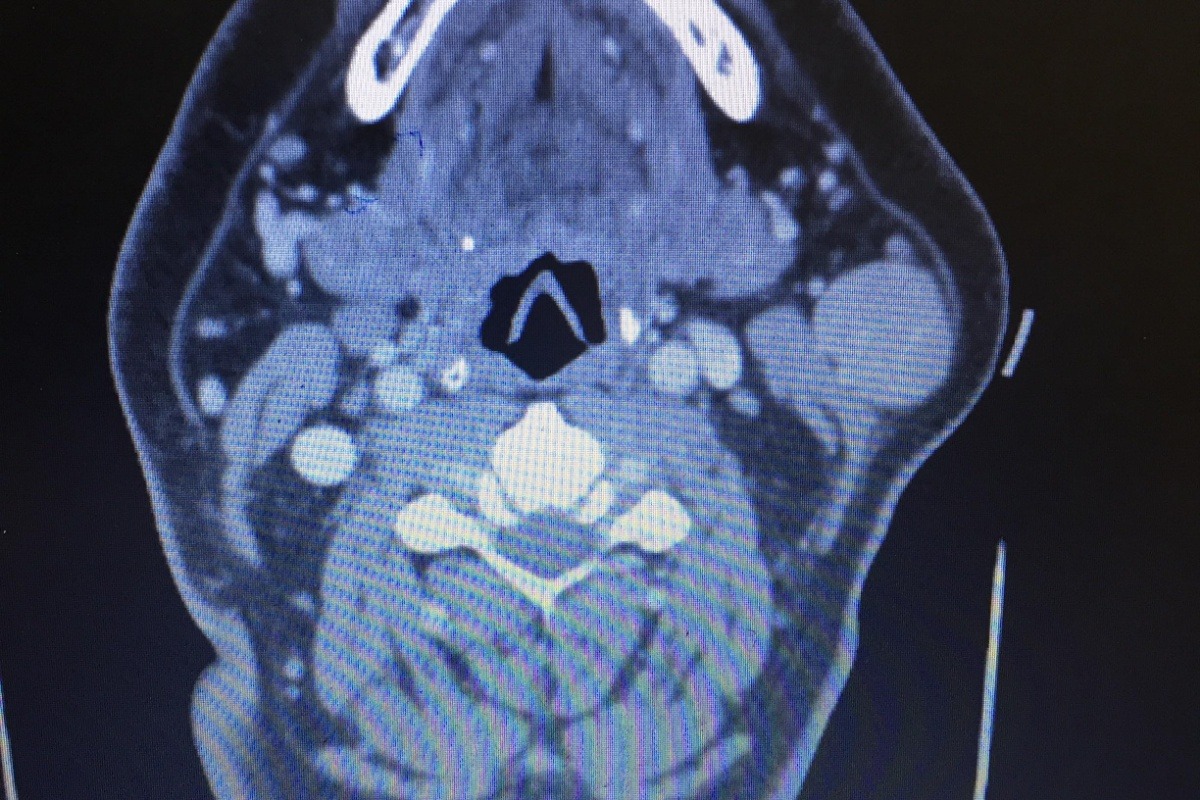

Hi everyone! I'm Stacey, a friend of Bubba's. I am starting this gofundme to help Bubba pay for his surgery that is scheduled for 9/11.  He needs to pay $4000 for the CT scan & the surgery, **$1500 has to be paid before surgery. He has already missed a week of work, and is expected to miss at least a week after having the surgery. When I spoke with Bubba he said, "It’s a Parotid Gland Tumor a little bigger than a golf ball just under my left jaw. It is benign but has to be removed for a couple reasons. 1. It’s sitting on nerves that control the left half of my face. 2. It could convert into cancer if left to grow. The surgery is tough they have to peel my face back to get to it and there’s a slight chance they cut a nerve cluster that controls half my face. If that happens I could end up with lack of control of half my face".  After hearing his concern about not being able to pay to have the surgery, I suggested starting a gofundme...Let's help Bubba get this painful tumor removed!!!